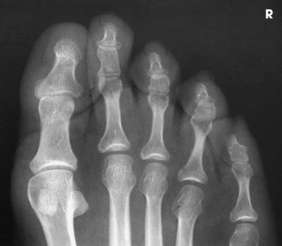

Each foot has 14 phalanges—2 in the great toe and 3 in each of the other toes. The phalanges of the great toe are termed the distal and proximal phalanges. The phalanges of the other toes are termed the proximal, middle, and distal phalanges. Each phalanx is composed of a body and two expanded articular ends—the proximal base and the distal head.

The five metatarsals are numbered one to five beginning at the medial or great toe side of the foot. The metatarsals consist of a body and two articular ends. The expanded proximal end is called the base, and the small, rounded distal end is termed the head. The five heads form the “ball” of the foot. The first metatarsal is the shortest and thickest. The second metatarsal is the longest. The base of the fifth metatarsal contains a prominent tuberosity, which is a common site of fractures.

Beneath the head of the first metatarsal are two small bones called sesamoid bones. They are detached from the foot and embedded within two tendons. These bones are seen on most adult foot radiographs. They are a common site of fractures and must be shown radiographically (see Fig. 6-2).